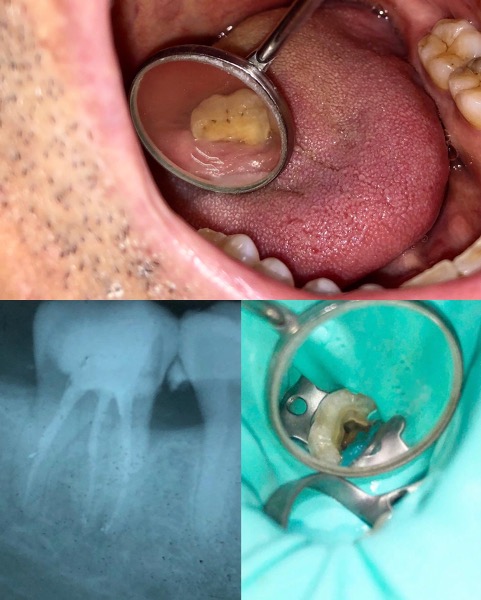

Una corretta terapia canalare con un perfetto sigillo a livello degli apici delle radici è fondamentale. I denti devitalizzati impropriamente possono creare ulteriori problemi che poi andranno a ripercuotersi sulle cure effettuate successivamente come le ricostruzioni e le corone protesiche con conseguente fallimento del piano terapeutico.

Capita spesso di incontrare denti già devitalizzati in maniera impropria che necessitano, seppur asintomatici, di essere ritrattati per evitare che i granulomi infetti visibili radiograficamente si evolvano riassorbendo tutto l’osso sottostante.

Un adeguata endondonzia serve per salvare quei denti che altrimenti sarebbero destinati ad essere estratti. Quando un dente viene devitalizzato viene privato della sua irrorazione sanguigna e del nutrimento, rendendo la sua struttura più “vetrosa” quindi più fragile e soggetta a fratture. Per questo motivo è consigliabile nella maggior parte dei casi capsulare i denti una volta che hanno perso la loro vitalità.